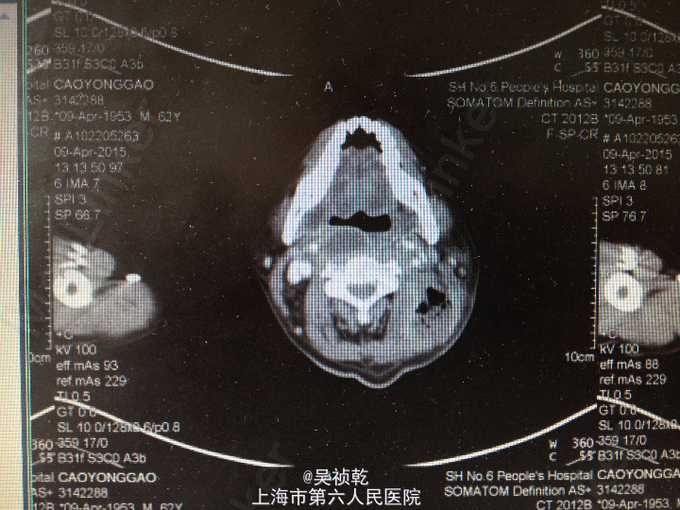

查体:神志清醒,呼吸稍促,推入病房,发育正常,营养良好,自主体位。皮肤粘膜:无黄染,无瘀点瘀斑,无贫血貌,无肝掌,无蜘蛛痣。淋巴结:全身浅表淋巴结可触及肿大。双侧颌下淋巴结肿大,左侧颈部肿大,皮肤红肿,皮温偏高,局部有波动感。头颈部:无头颅畸形,无巩膜黄染,无结膜苍白 ,口唇无紫绀,无扁桃体肿大。颈软,气管居中,甲状腺无肿大,无颈静脉怒张。胸部:胸廓无畸形,心率105次/分, 节律齐,无杂音,两肺呼吸音清,未及啰音。腹部:腹部平坦,腹壁柔软,全腹无压痛、无反跳痛,肝脏肋下未触及,脾肋下未触及,肝区无叩击痛,肾区无叩击痛。无移动性浊音,肠鸣音正常。肛门、直肠及外生殖器: 正常。脊柱与四肢:脊柱无畸形,四肢无畸形,四肢活动自如。神经系统:生理反射存在,病理反射未引出。 辅检:2015-4-8 血气检验报告:二氧化碳分压 34.7 mmHg ↓,氧分压 60.9 mmHg ↓,氧饱和度 91.8 % ↓。门诊化验检验报告:凝血酶原时间 13.1 秒 ,国际标准化比率 1.19 ↑,部分凝血活酶时间 30.4 秒 ,D二聚体 1.13 mg/L FEU ↑,纤维蛋白(原)降解产物 6.4 mg/L ↑。 生化检验报告:肌钙蛋白-I 0.013 ,CKMB 1.4 ug/L ,肌红蛋白 28.6 ug/L 。 生化检验报告:血清钾(干式) 4.5 mmol/L ,血清钠(干式) 137 mmol/L ↓,血清氯(干式) 94 mmol/L ↓,总蛋白(干式) 66 g/L ,白蛋白(干式) 32 g/L ↓,谷丙转氨酶(干式) 26 U/L ,谷草转氨酶(干式) 16 U/L ,γ-谷氨酰酶(干式) 19 U/L ,碱性磷酸酶(干式) 103 U/L ,总胆红素(干式) 16 μmol/L ,尿素(干式) 7.5 mmol/L ↑,肌酐(干式) 67 μmol/L ,尿酸(干式) 154 μmol/L ↓,淀粉酶(干式) <30 U/L ↓,血糖(干式) 22.0 mmol/L ↑,B型钠尿肽前体(proBNP) 199.80 ng/L ↑。 2015-4-9 血常规检验报告:白细胞 13.2 X10^9/L ↑,红细胞 3.76 X10^12/L ↓,血红蛋白 125 g/L ↓,细胞比积 35.8 % ↓,血小板 261 X10^9/L ,淋巴细胞百分比 4.7 % ↓,中性细胞百分比 84.4 % ↑。糖尿病医学中心检验报告:糖化血红蛋白 12.40 % ↑。 颈部超声示:双侧颌下淋巴结肿大,左侧颈后软组织结构紊乱,内混合回声及肿大淋巴结,考虑炎性改变可能,建议治疗后复查。 颈部CT:1.咽后间隙、左侧咽旁间隙及颈动脉鞘软组织明显肿胀、渗出,颈部多发肿大淋巴结,考虑炎症可能大,请结合临床并门诊增强CT评估。2.左侧甲状腺小结节可能,请结合临床,必要时随访。 2015-4-9 颈部增强CT示:颈部及胸腔纵隔脓肿形成。 2015-4-8引流分泌物培养结果: 肺炎克雷伯菌。

患者入院时诊断为:1.左颈部脓肿,颈部软组织感染,纵膈脓肿形成。2.糖尿病。 入院后予对症处理:1.加强抗感染,予万古霉素+磷霉素联合。2.床边行脓肿切开引流,引流液送培养。2、予吸氧、禁食、营养支持等对症治疗。3.病情危重,告知家属相关风险,予告病危。4.进一步完善颈部及胸部增强CT,病请五官科会诊。 2015.04.09CT提示颈部,咽后壁及胸腔纵隔脓肿形成,故请五官科及胸外科会诊,会诊意见为:手术切开引流。故于4.9全麻下行颈部脓肿清创引流术。 手术过程:患者取仰卧位,肩部垫高,全麻达成后,常规消毒铺巾。在胸骨切迹上约两横指处顺皮纹方向作弧形领式切口,长约8cm。依次切开皮肤、皮下组织和颈阔肌。游离颈阔肌深面间隙,在其深面用电刀分离皮瓣,上至甲状软骨切迹,下至胸骨切迹,两侧越过胸锁乳突肌前缘。分离右侧胸锁乳突肌,分离至咽后间隙,咽后间隙内见大量脓液,予双氧水,稀碘伏水,及生理盐水彻底冲洗脓腔。术中请胸外科会诊认为目前上纵隔脓肿暂无需处理。左右各置一根颈部引流管;仔细止血;清点器械无误后,缝合皮下及皮肤层。术中出血少未输血,术程顺利,病人安返。 术后诊断:1.左颈部脓肿,颈部软组织感染,纵膈脓肿形成。2.糖尿病。3.全身感染症状。4.吞咽困难。 术后结合药敏结果,继续予万古霉素+磷霉素联合抗炎,引流管予生理盐水持续冲洗引流,目前引流液不多,术后一周复查CT见脓肿明显缩小,纵膈脓肿有所缩小,目前治疗方案:1.停用原抗菌方案,换用莫比沙星 0.4 qd 静滴,每次滴注90min;2.每3天复查血象,及时复查颈部CT,治疗5天后再评估,一般情况好可停药随访;3.糖尿病患者,注意血糖变化,监测心功能及肝肾功能。